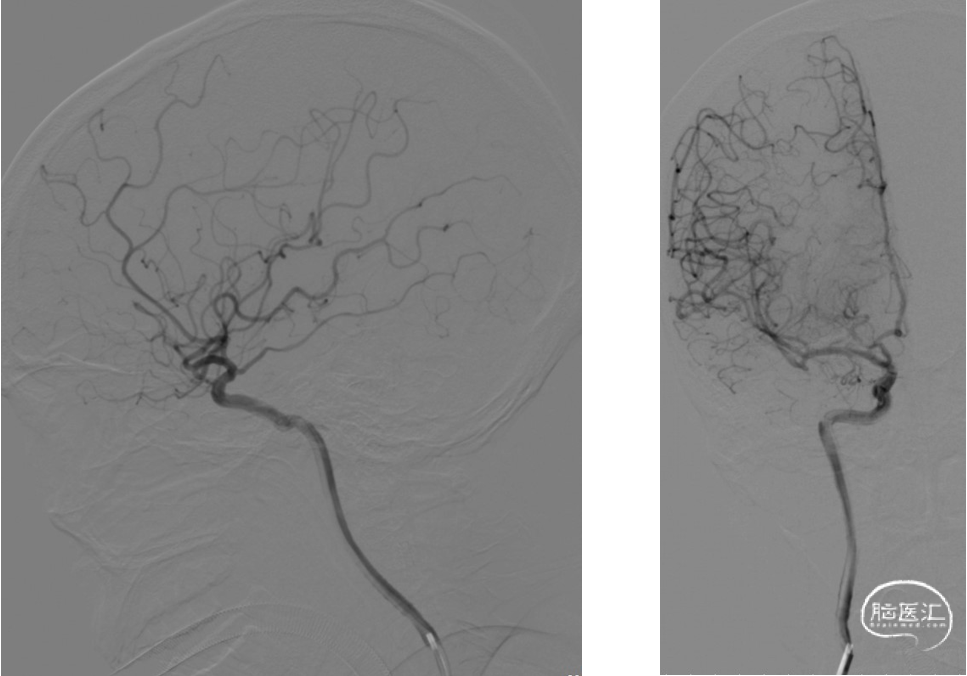

左侧颈总动脉正侧位造影

右侧颈内动脉正侧位造影

复查造影动脉瘤少量充盈,继续将3枚1mm*3cm弹簧圈(EV3)沿子瘤的Echelon-10微导管送入。复查造影示左侧颈内动脉、左大脑中动脉、大脑前动脉、左侧后交通动脉显影良好,动脉瘤栓塞完全。